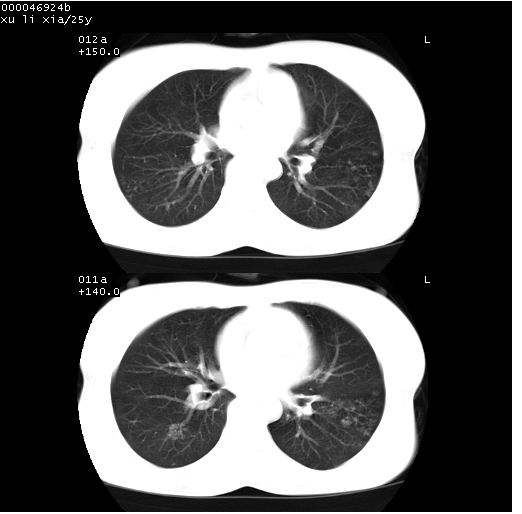

患者 女,25岁。因“左侧卵巢肿瘤”术前胸片偶然发现两肺病变。平素无明显不适,无呼吸系统症状及体征,无传染病史。

cr x线胸片提示:两肺感染性病变(结核可能性大)。

胸部ct轴位平扫(层厚10mm,螺距1.5,重建间隔10mm),图像如下:

(注:上级医院会诊胸部ct片——考虑为肺部真菌感染。)

病灶呈地图样分布于肺外围,与正常组织分界清晰+弥漫性磨玻璃影中见小叶间隔增厚呈碎石路样表现+年轻女性,无明显临床症状=肺泡蛋白沉积症?

平行于间质走行微结节影;拌钙化灶;分布通气好的肺野